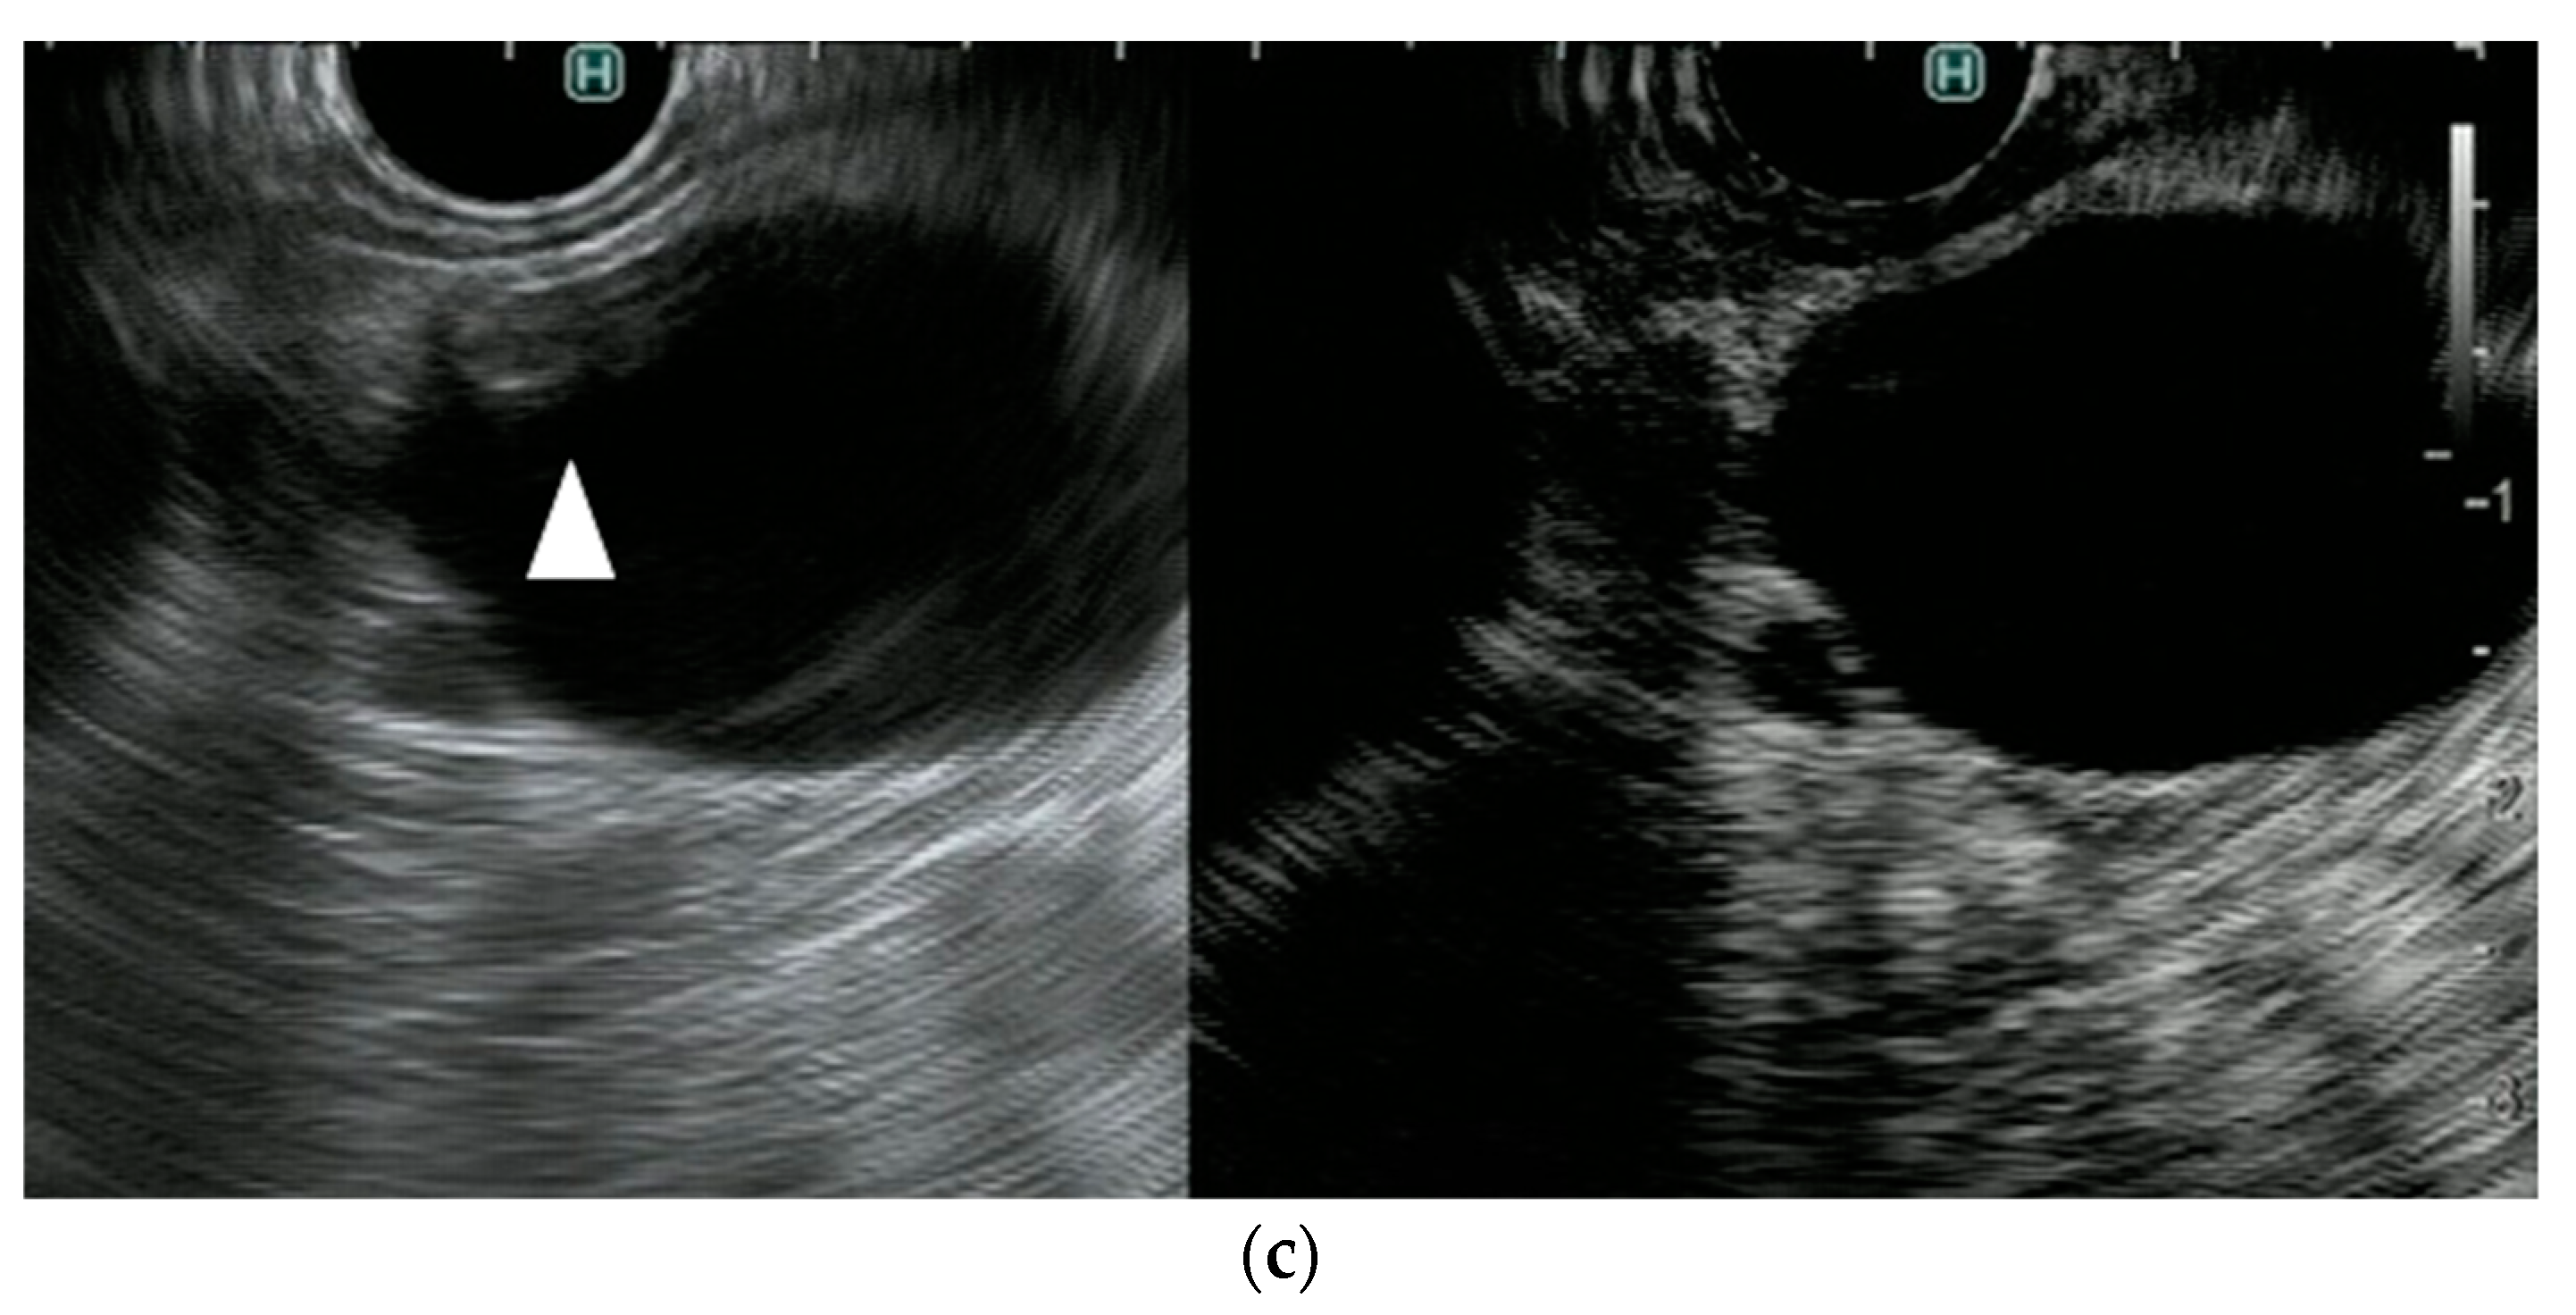

- Yamashita, Y.; Yoshikawa, T.; Kawaji, Y.; Tamura, T.; Hatamaru, K.; Itonaga, M.; Ida, Y.; Maekita, T.; Iguchi, M.; Murata, S.I.; et al. Novel endoscopic ultrasonography imaging technique for visualizing microcirculation without contrast enhancement in subepithelial lesions: Prospective study. Dig. Endosc. 2020, 33. [Google Scholar] [CrossRef]